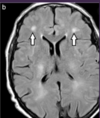

DX?

Infarto cerebral debido a ACM izq